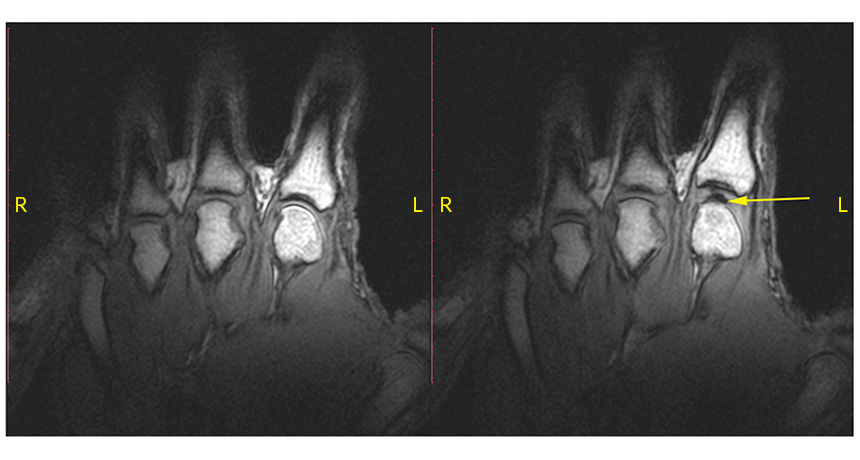

KNUCKLING DOWN A knuckle at rest (left) pops when pulled. The sound of the knuckle cracking comes from a bubble (right, arrow) opening in the joint.

G.N. Kawchuk et al/PLOS ONE 2015 (CC BY 4.0)